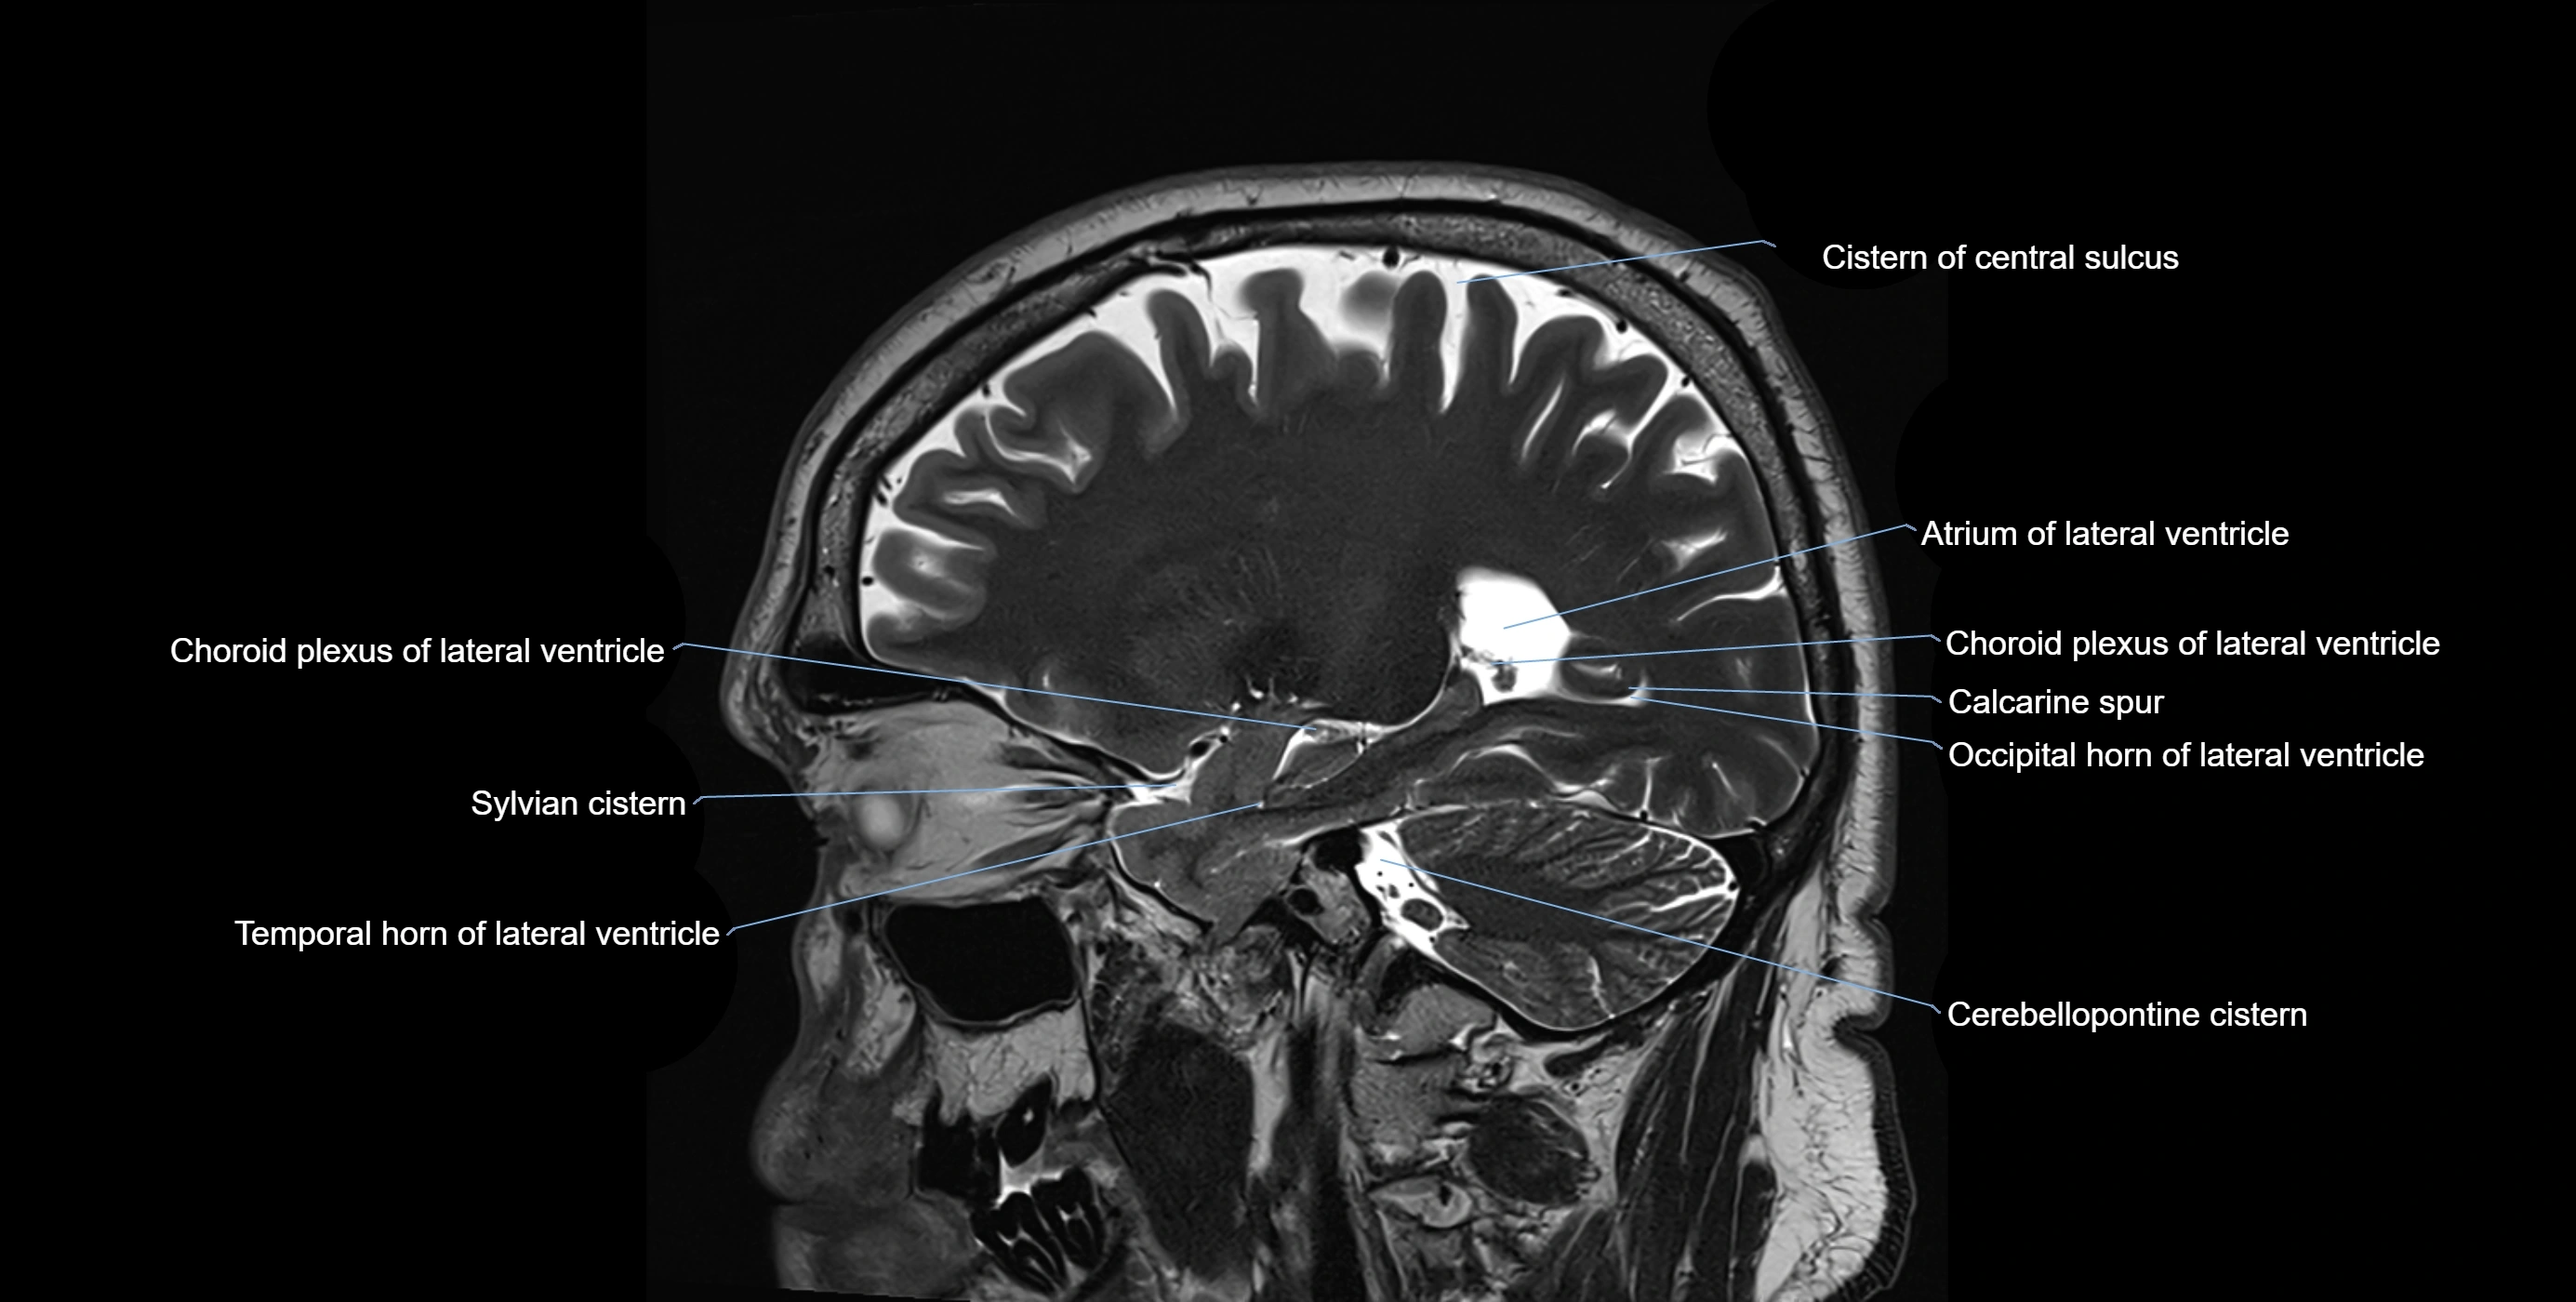

CT image

image